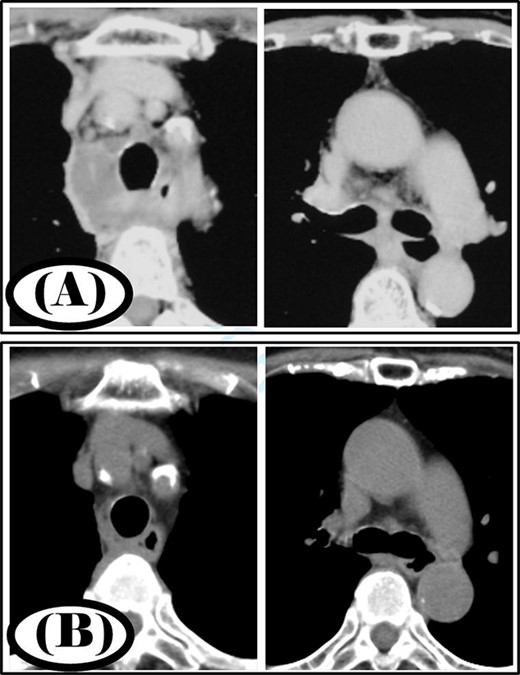

A 68-year-old woman was diagnosed with a posterior pharyngeal abscess triggered by a fever and sore throat. Cervicothoracic CT showed that the infection had spread to the mediastinum (Fig. 3A), and the patient was diagnosed with type IIB DNM. Cervical drainage and mediastinal drainage were performed simultaneously. Mediastinal drainage using only the cervical approach was sufficient. Streptococcus sanguinis was detected in the mediastinal abscess cavity. Continuous irrigation with saline (2 l/day) was initiated immediately post-surgery. The duration of irrigation, drainage and hospital stay were 10, 13 and 22 days, respectively. Four weeks post-surgery, cervicothoracic CT showed no abscess cavity and an improvement in infection was noted (Fig. 3B).

Case 3: pre- and post-treatment cervicothoracic CT; (A) pre-operative cervicothoracic CT and (B) cervicothoracic CT 4 weeks after treatment.